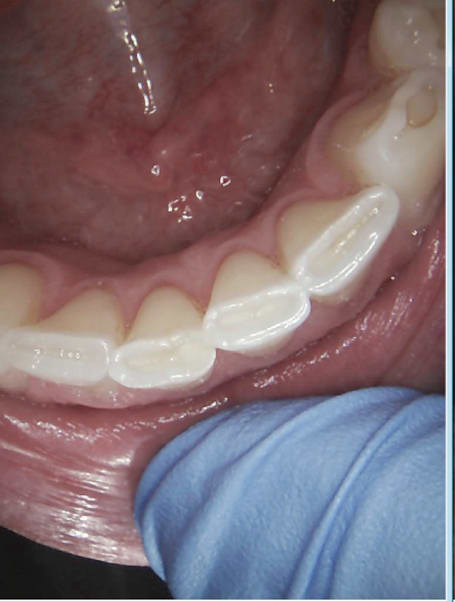

On cote quoi là ? -)

25 36 ? -)

Exemple type de radio rétro coronaire avec capteur, les 34, 44 sont difficiles à avoir.

Les rebords rétro alvéolaires aussi on a du mal a bien centrer le plan occlusal.

Capture d e cran 2016 02 18 09.18 - Eugenol